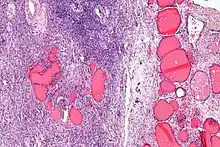

| Micrograph of a struma ovarii. Characteristic thyroid follicles are seen on the right, and ovarian stroma on the left. H&E stain. | |

A struma ovarii (literally: goitre of the ovary) is a rare form of monodermal teratoma that contains mostly thyroid tissue, which may cause hyperthyroidism.[1]

The vast majority of struma ovarii are benign tumours; however, malignant tumours of this type are found in a small percentage of cases.[2]